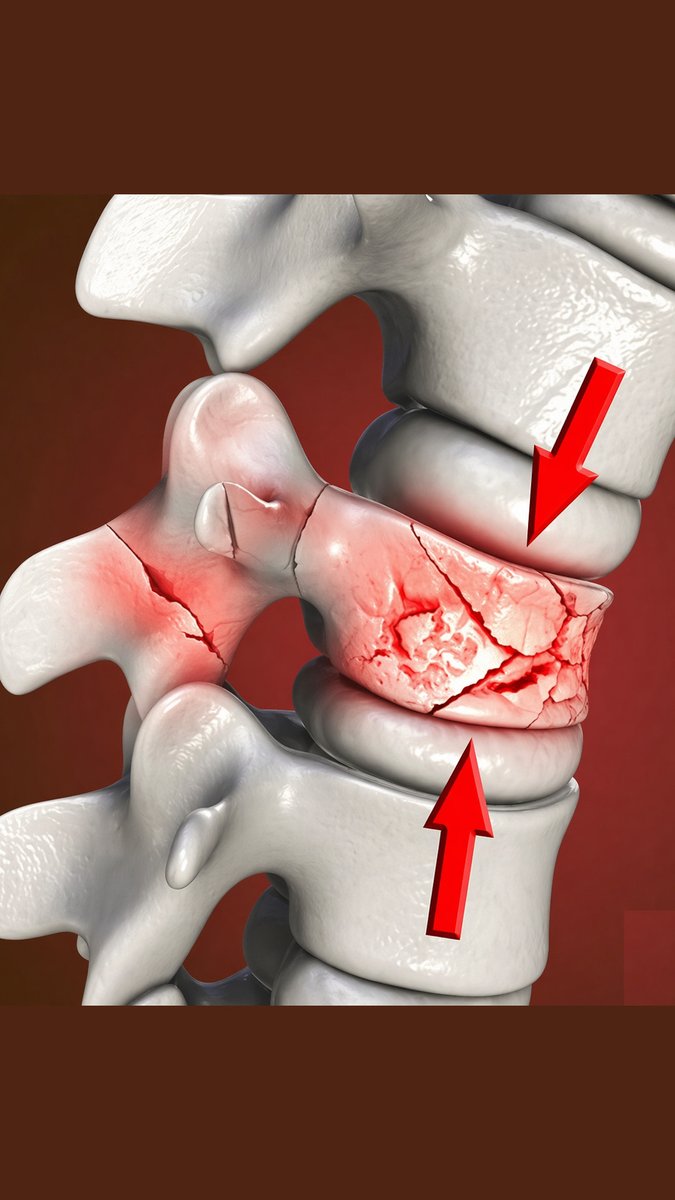

What fracture type is this? Look closely at the vertebral body—can you identify the pattern of compression and fragmentation? Drop your answer below 👇 and see if you caught this classic injury. Read: tinyurl.com/3mbmvy2b #orthopedics #radiology #xray #mededucation

MedEd_Cases's tweet image. What fracture type is this?

Look closely at the vertebral body—can you identify the pattern of compression and fragmentation? Drop your answer below 👇 and see if you caught this classic injury.

Read: tinyurl.com/3mbmvy2b

#orthopedics #radiology #xray #mededucation